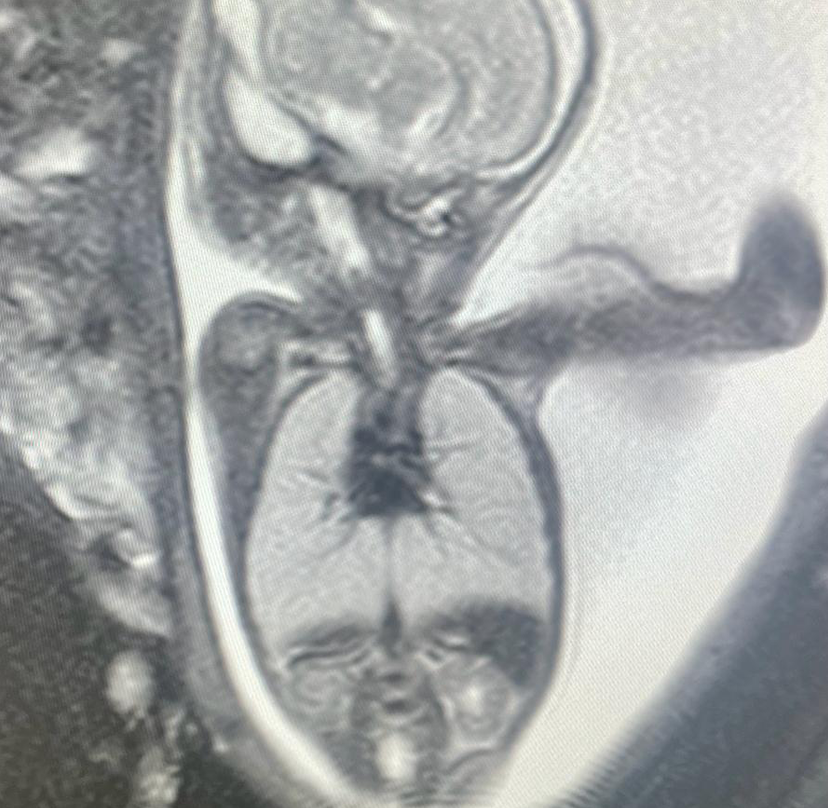

Reaching inside the uterus to assist a troubled foetus is known as foetal intervention. Over the past few decades, we have made such remarkable progress in foetal issue detection. Only a small number of disorders need treatment prior to birth, despite the fact that many may now be correctly detected before birth using genetic and imaging techniques. The treatments listed below can be used to fix these mostly minor anatomical issues that continue to harm the developing foetus.

Foetal intervention can be done using one of three general strategies, all of which were created recently. Open foetal surgery is the most conclusive and intrusive.